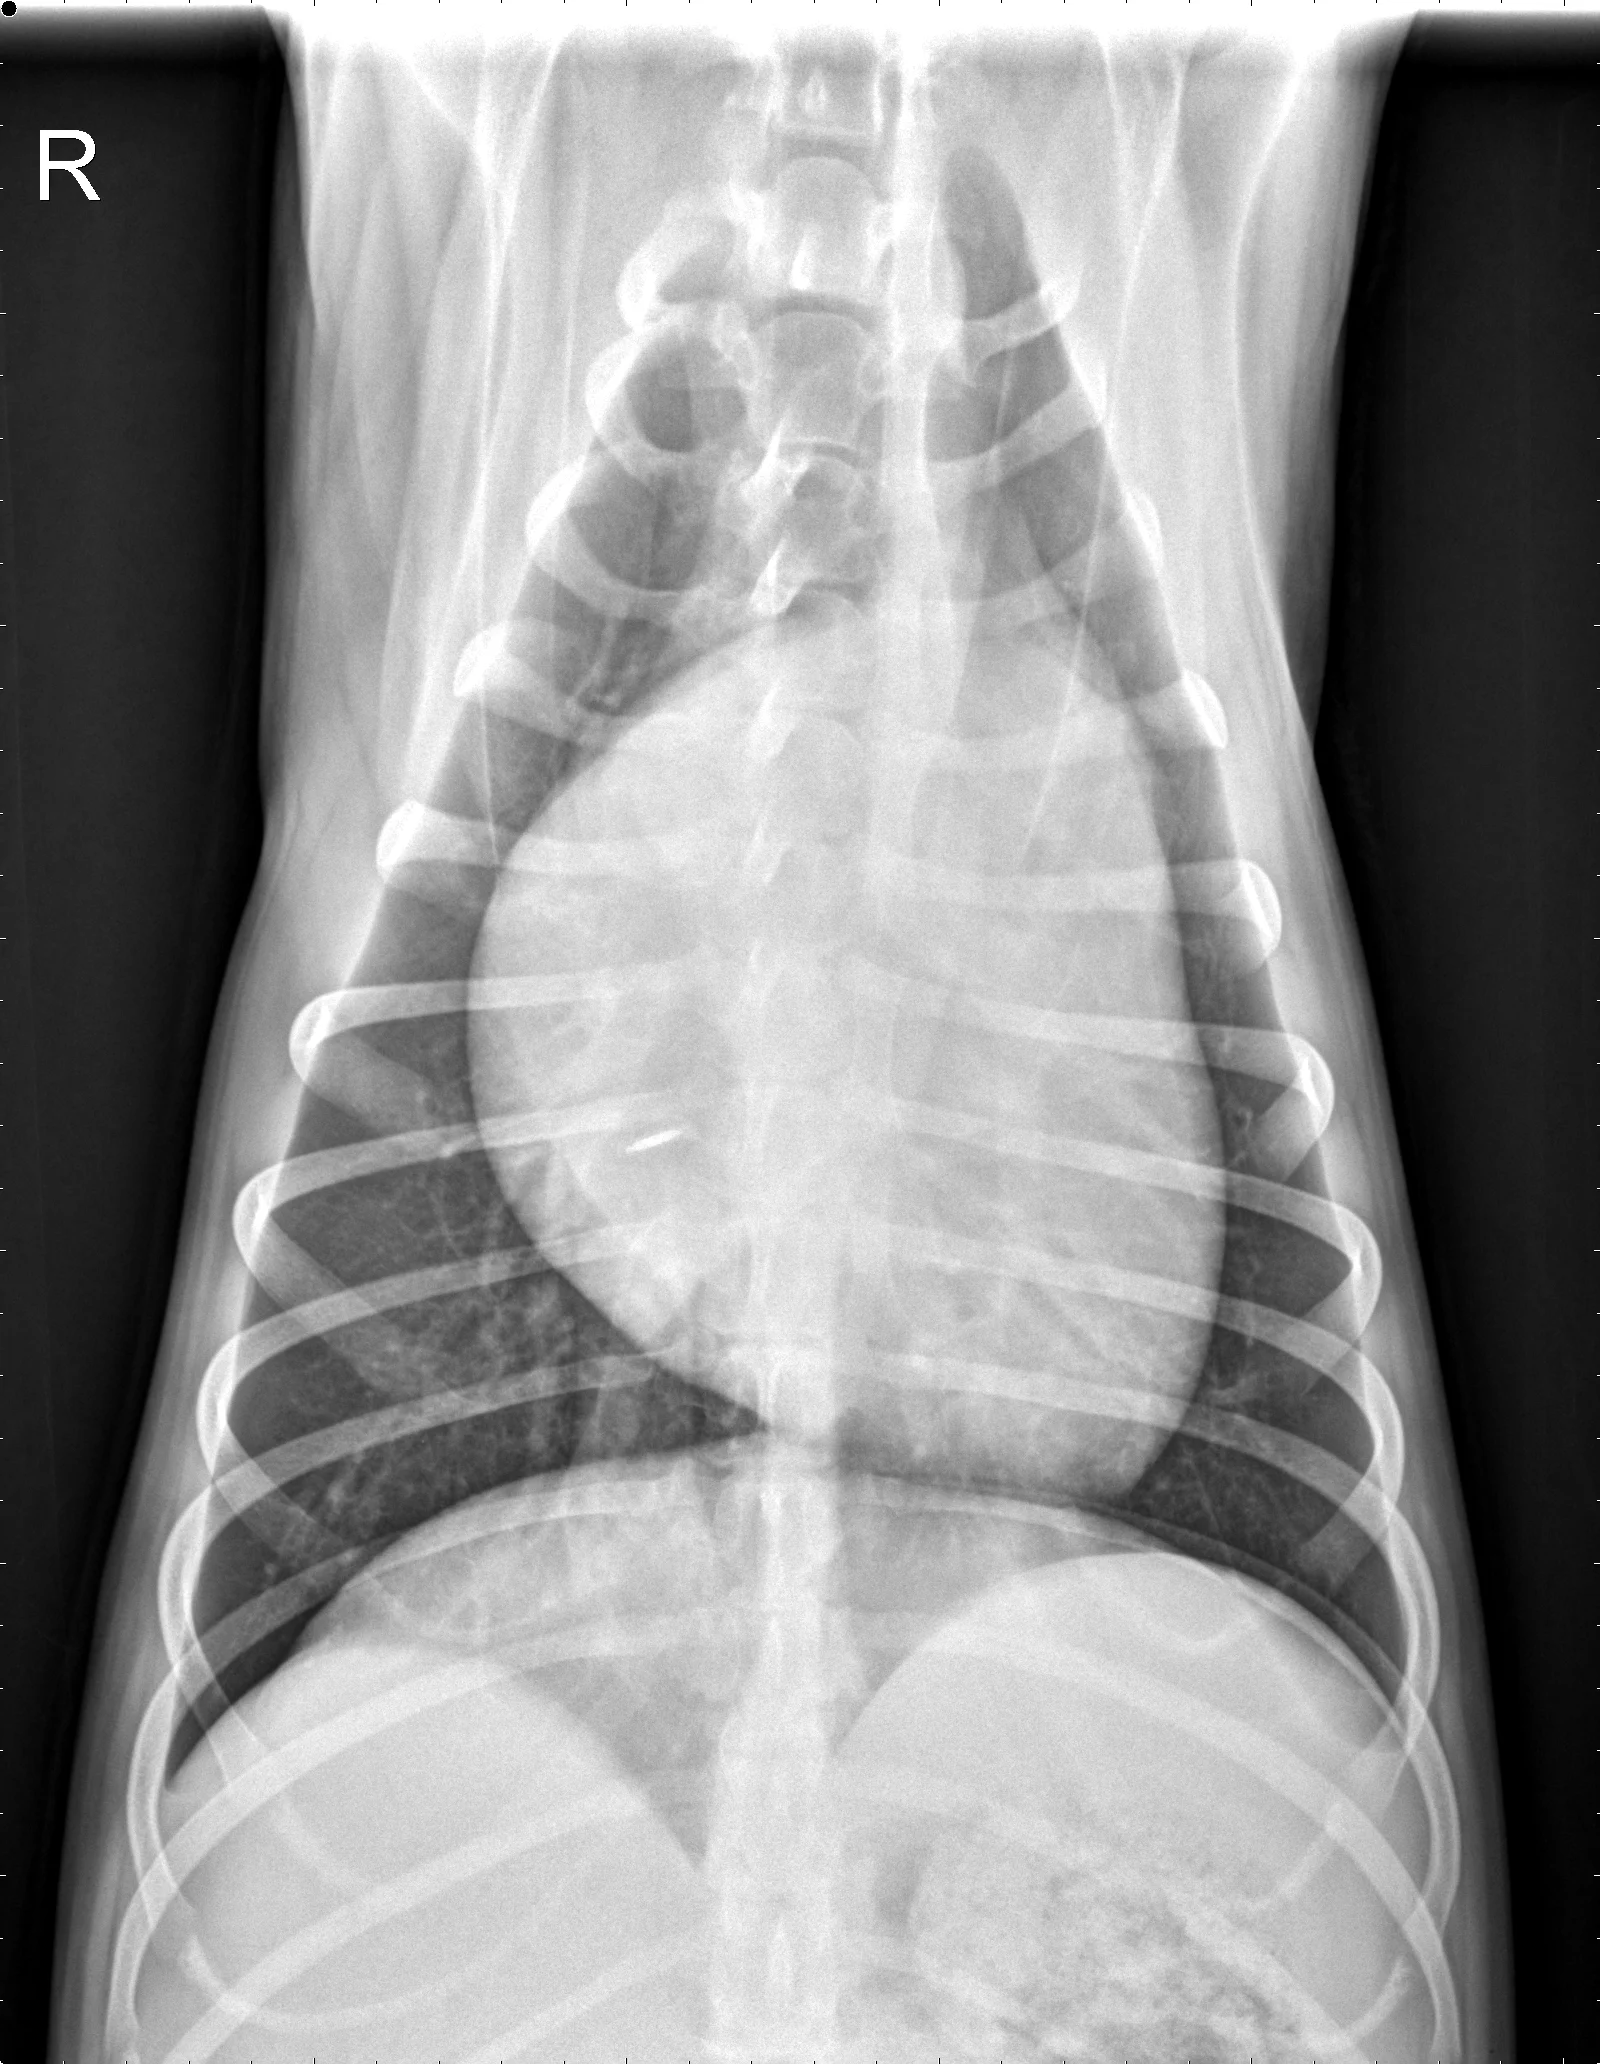

At least 2 orthogonal views, ideally taken during peak inspiration, are necessary for appropriate radiographic study of the cardiovascular system; however, a 3-view study is ideal for comprehensive evaluation of the thorax. Some differences should be considered when deciding to acquire a right versus left lateral projection and a dorsoventral (DV) versus ventrodorsal (VD) projection. On the left lateral view, the cardiac silhouette is typically more rounded and the apex is further elevated from the sternum than in the right lateral view (Figure 1). In the DV view, the cardiac silhouette is commonly displaced cranially and to the left by the diaphragm and appears more rounded than in the VD view. The caudal pulmonary vasculature is better delineated in the DV view, whereas the lung field (particularly the accessory lobe) is better evaluated in the VD view (Figure 2).

FIGURE 2 Normal DV (left) and VD (right) projections of the thorax in a large, crossbreed dog. The cardiac silhouette appears more rounded, and the caudal pulmonary vasculature is more apparent (arrowheads) in the DV view compared with the VD view. In some DV projections, the cardiac silhouette can appear significantly displaced to the left (not apparent in this case). Images courtesy of Federico Villaplana Grosso, DACVR, DECVR